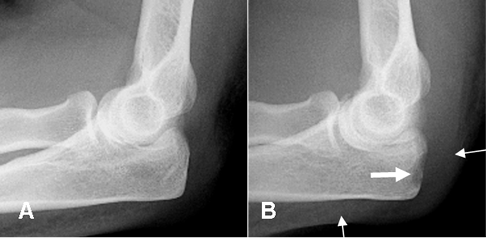

Fig 27 A. Osteomielitis.

A y B: Rx lateral. Inicialmente no se encuentran alteraciones. Después hay prominencia de los tejidos blandos, con obliteración de los planos grasos. (Flechas delgadas) y área de osteolisis en la parte posterior del olécranon, por osteomielitis. (Flecha gruesa).